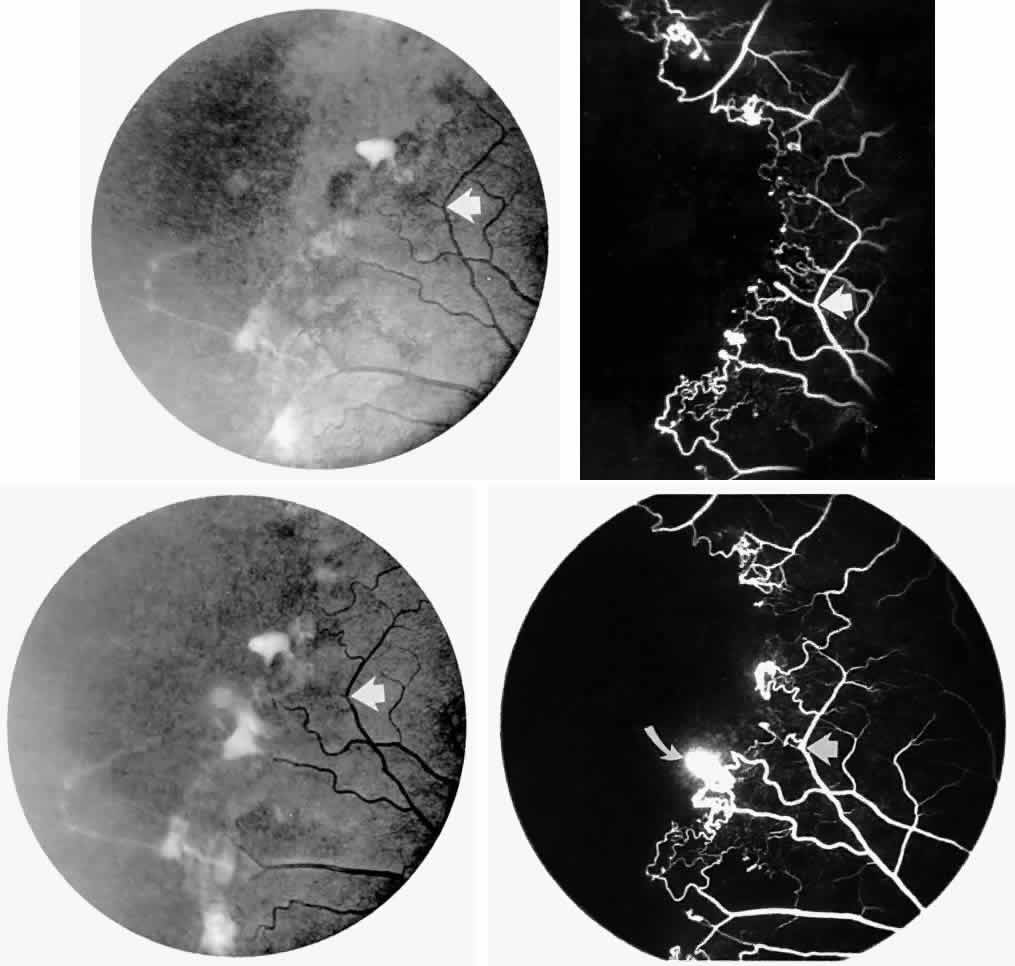

STAGE III: PRERETINAL NEOVASCULARIZATION (PROLIFERATIVE SICKLE RETINOPATHY). “Sea fan”-shaped neovascularization typically develops on the venular side of an arteriolar-venular anastomosis, mimicking the normal development of retinal capillaries (Fig. 24).125 A lowered oxygen tension and angiogenic factors released on the venular side may be the stimulus for neovascular growth.125,126 In most instances, the direction of growth is toward the ora serrata, from the perfused retina toward the nonperfused retina. Presumably, this represents an abortive attempt to revascularize the nonperfused retina, initiated by vasoproliferative factors.

Fig. 24. A. Photograph of the peripheral retina, demonstrating several small fibroglial membranes. B. Fluorescein angiogram corresponding to A, showing multiple arteriolar-venular anastomoses with early sea fan formation. C. Photograph of the same area 2 years later demonstrates more fibroglial membranes. D. Fluorescein angiogram corresponding to C shows new sea fans caused by an arteriolar-venular anastomosis (curved arrow). Large arrow (A through D) identifies corresponding arteriolar bifurcation.

The characteristic neovascular lesions of PSR are called sea fans because they resemble the marine invertebrate Gorgonia flabellum.70 They tend to occur more commonly in the temporal periphery, but they have been reported to occur in the temporal macula in the presence of extensive nonperfusion.130,133 Initially they grow on the surface of the retina, but they often become elevated into the vitreous and adhere to a partially detached posterior hyaloid.114 It may be difficult to visualize small sea fans ophthalmoscopically; however, fluorescein angiography clearly demonstrates leakage of dye into the vitreous (Fig. 25). The feeding arteriole is usually more tortuous than the draining venule (Fig. 26). Early on, the neovascular lesion is fed by a single arteriole and drained by a single venule, but with time, additional arterioles and venules become arborized within the lesion (Fig. 27).129 Growth of the sea fan often occurs circumferentially, rather than radiallyÜmh- 1Ý, toward the ora serrata. Progressive circumferential growth may lead to neovascular lesions extending around the entire periphery. As it matures, a white fibroglial mantle often covers the neovascular tissue (Color Plate 2B).